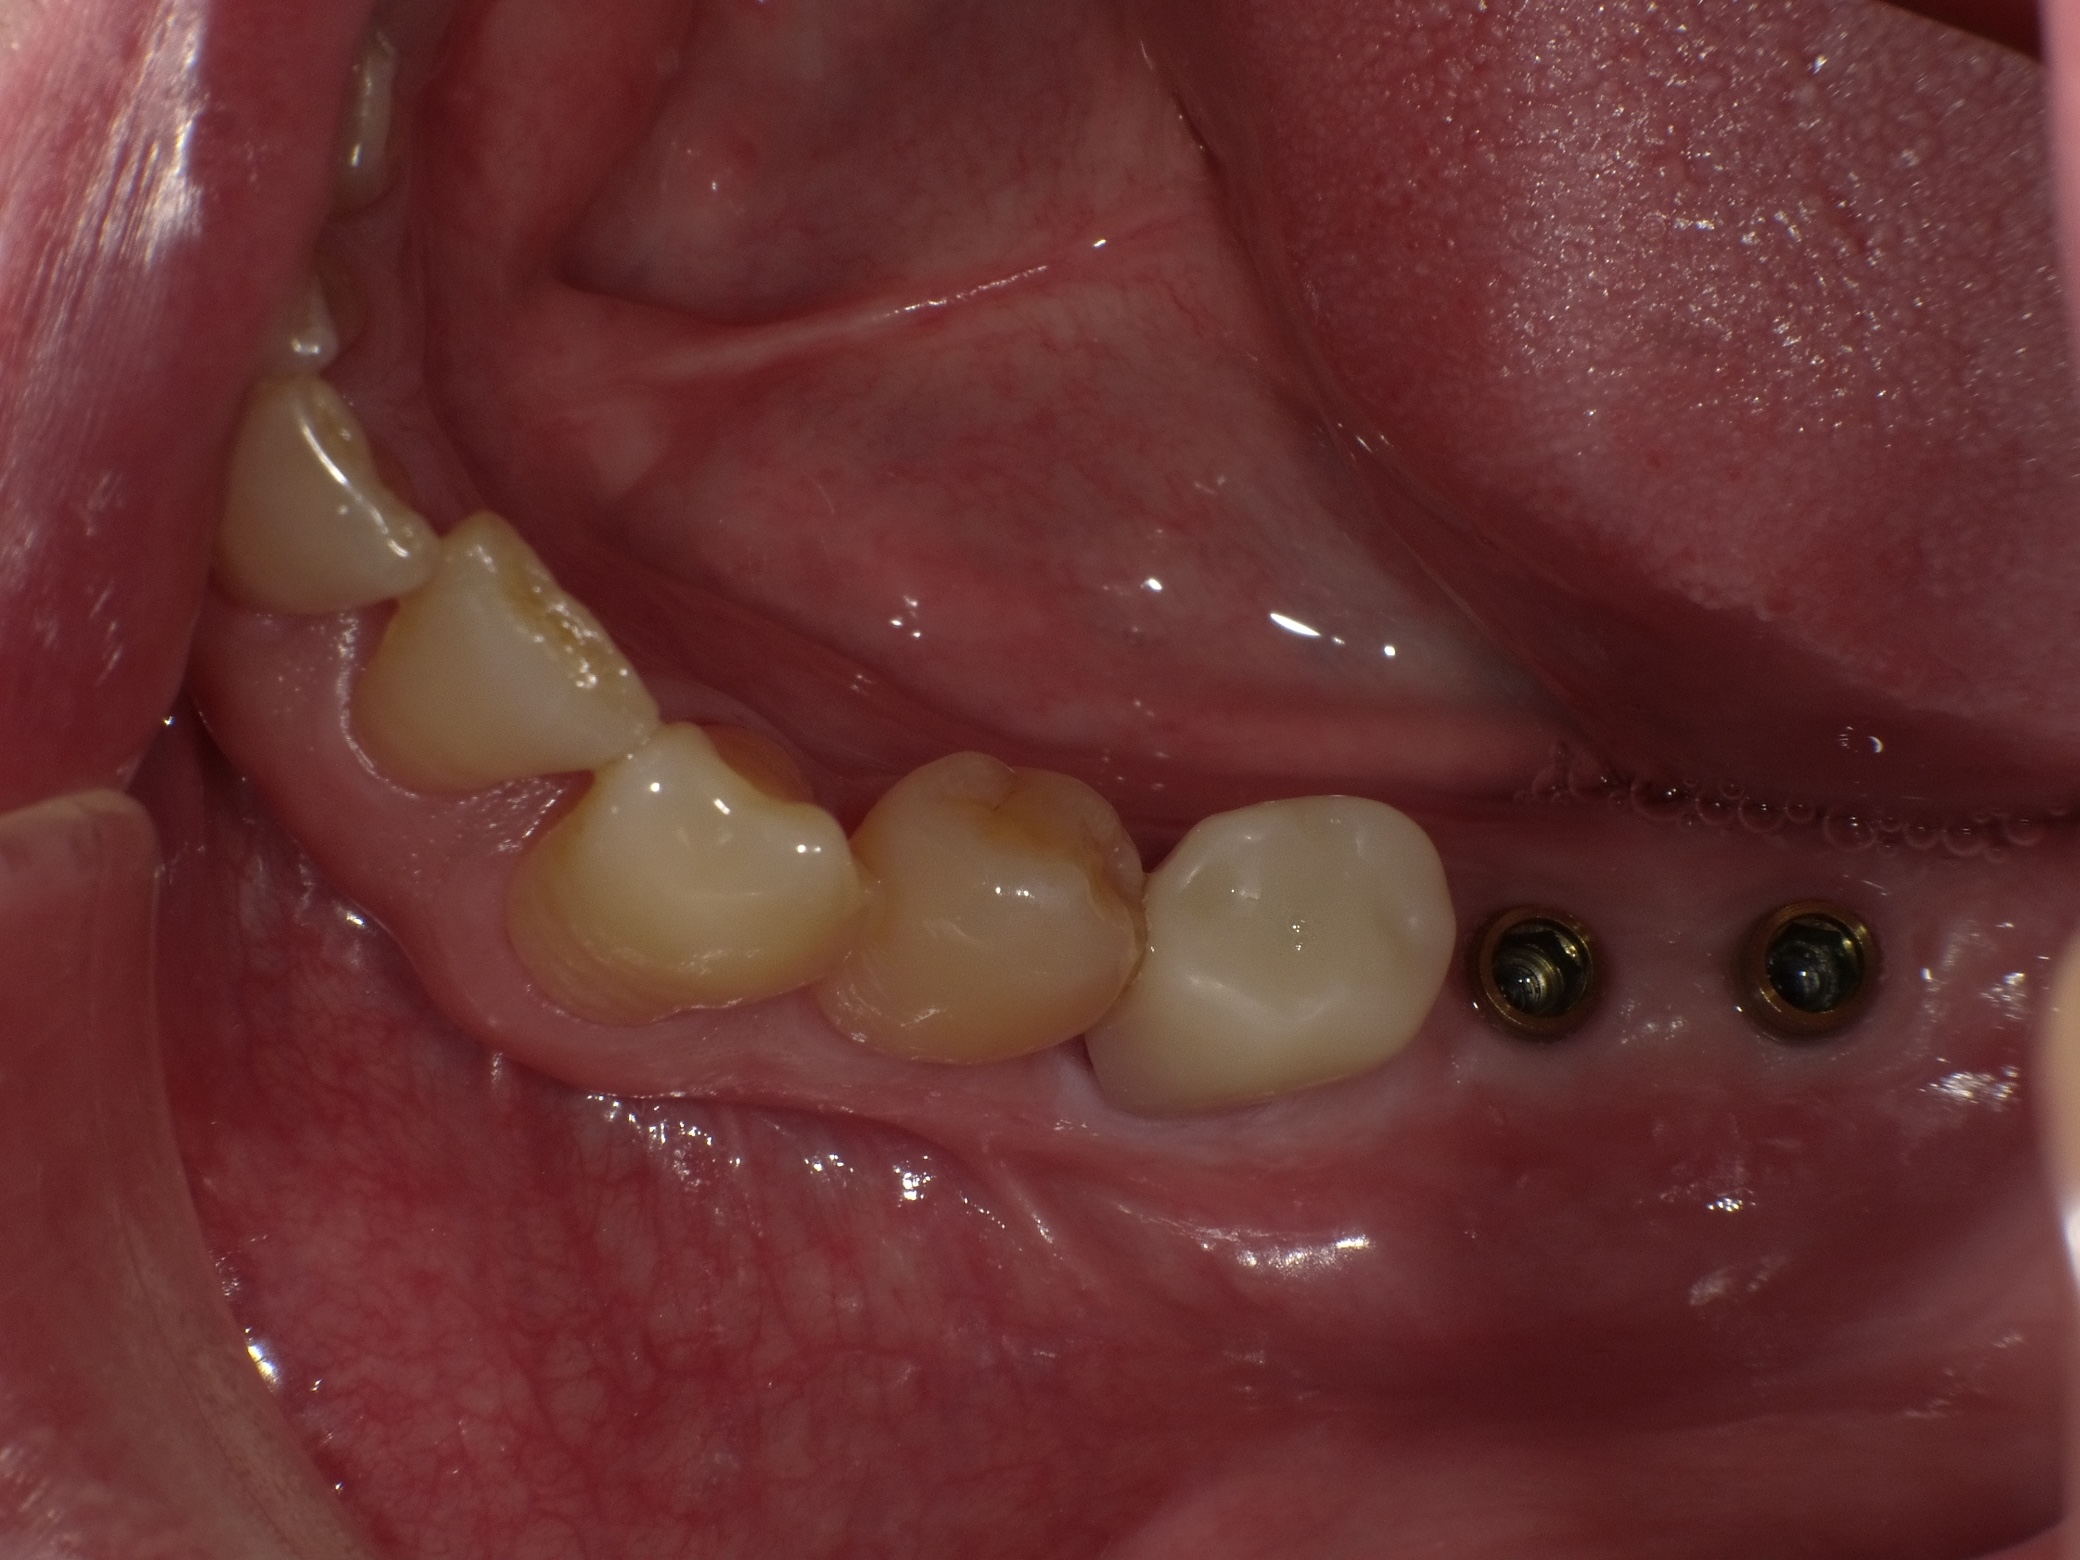

左下2本インプラント症例

主訴 奥歯でしっかり咬めるようにしたい(男性) 治療内容 左下の奥歯2本をインプラントにて治療しています。プラマRFインプラントを埋入。

手術後3ヶ月待ち、骨とインプラントが固まったことを確認し、二次手術後に型取りを行っています。当院では、ほとんどの症例でデジタルでの型取りを行っています。

インプラントを埋入した部位に型取り用のパーツをはめ、3Dスキャナーにて型取りをし、ジルコニアクラウンの被せ物を作製しています。完成後の咬合面は状態を確認後、埋めていきます。

治療期間 約4ヶ月

費用 総額 ¥700,000-(税別) リスクと副作用 ・外科治療となるので、お身体の状態によっては受けれない場合がある(広範囲に適用可能な治療ですが、個々の患者様の状況によって適用外な場合もある)

・術後に多少の痛みや腫れが出ることがある -